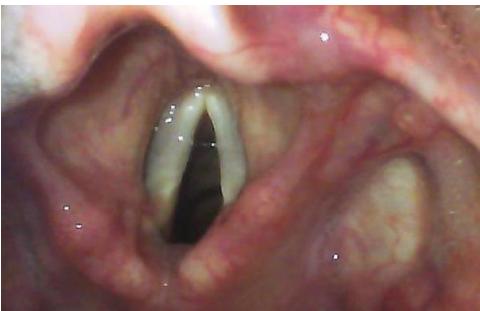

Endotracheal Tube (ETT) and Intubation

- Name of Equipment: Endotracheal Tube (ETT).

- Purpose: To maintain a definitive airway, provide maximum oxygenation/ventilation, and prevent aspiration.

- Indications:

- GCS (unable to protect airway).

- Comatose patients or cardiac arrest.

- Respiratory failure.

- Confirmation of Placement:

- Primary (Clinical):

- Chest rise.

- Seeing the tube pass through the vocal cords.

- Bilateral breath sounds (5-point auscultation: epigastrium first, then left/right bases and axillae). - CO2 fog inside the tube.

- Secondary (Equipment):

- Capnography/ETCO2 detector (Gold standard).

- Pulse oximetry.

- ABG.

- Chest X-ray (to verify tip position above the carina).